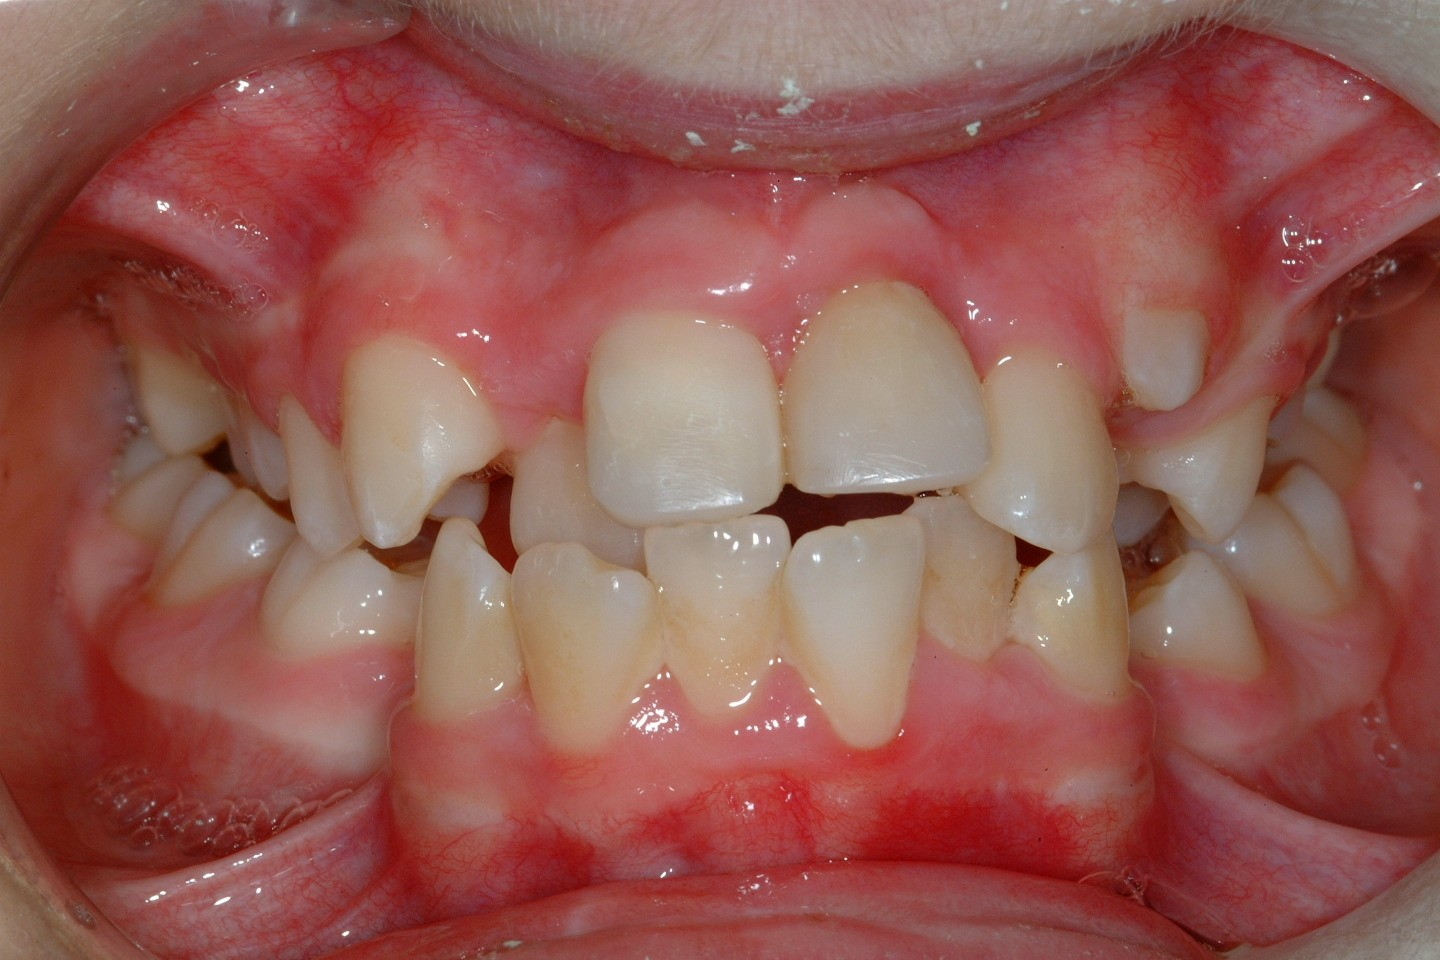

If problems with impacted or ectopic canines are identified and addressed early, chances of success are high with relatively minor interventions. If, however, the problem is not identified until later in life then other treatment options are required, frequently involving both orthodontic treatment and surgery. Treatment planning needs to take account of general factors, including issues such as patient desire, expectation and co-operation (Figure 17).

Management options are protean and should be fully discussed with the patient and parents/carers prior to any definitive treatment planning decisions. Informed consent should be sought as what could be a routine, though complex treatment for a patient during their adolescence, if delayed may become extremely difficult later in life.

Observation can be performed clinically, including vitality testing of adjacent teeth, and radiographically using a number of techniques. There are, however a number of potential problems that need to be considered before it is decided to leave the canine under observation. An ectopic canine can occasionally cause severe root resorption of adjacent teeth and this is often apparent only on radiographic investigation whilst being unsuspected clinically.

In view of the potential long-term problems that can arise if no active treatment is undertaken, all options need to be discussed carefully. Patients with ectopic canines often have acceptable aesthetics and function, unlike patients with other types of malocclusion. The benefits of treatment are consequently less obvious and only later in life will a problem present, such as when the deciduous canine is lost.